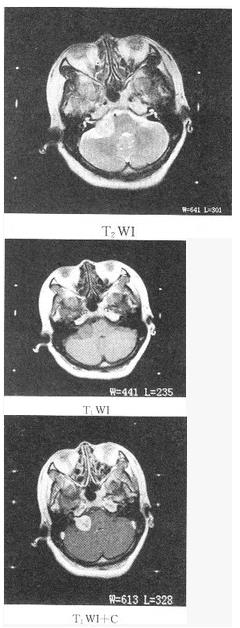

患者女性,42岁,右侧听力下降,MRI检查如图,最可能的诊断为()。

A、脑膜瘤

B、表皮样囊肿

C、三叉神经瘤

D、听神经瘤

E、脑梗死

D